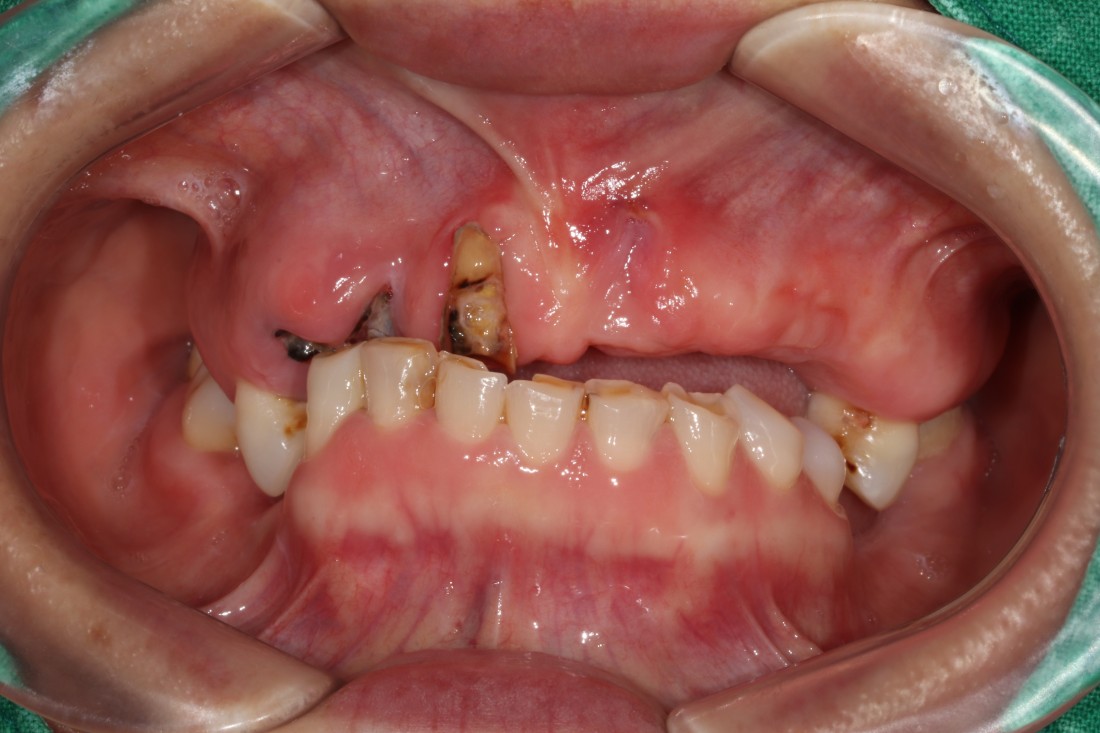

광주 상악임플란트를 해야하는 때가 오면

무엇보다도 '예쁘고 잘 씹어지게'

임플란트 진료를 받고싶으실텐데요.

광주 상악임플란트 치과는

4층 자체 치아기공소를 운영하고 있으며

보철물 디자인 퀄리티를

굉장히 중요하게 생각하고 진료하기 때문에

자연치아만큼 예쁘면서도

잘 씹어지는 광주 상악임플란트 진료를

보장할 수 있습니다.

만약 불편한 점이 생기셔도

자체 치아기공소에 바로 수정이 가능하여

빠르고 예쁘게, 잘 씹어지는

광주 상악임플란트를

완성하고 있습니다.